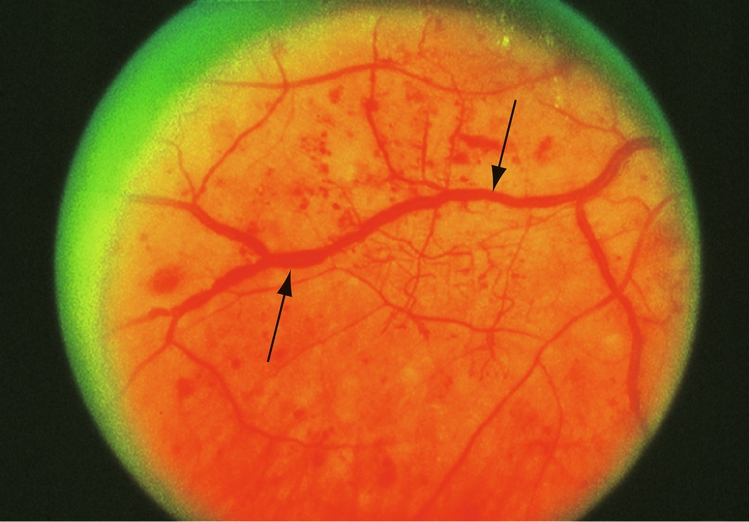

• anomalies (dilatations) veineuses dans 2 quadrants ou plus (fig. 5-8) ;

Figure 5-8

Rétinophotographie montrant les anomalies veineuses (beading) dans une RDNP (flèches).

(Photographie standard 6B, avec l'aimable autorisation de l'ETDRS.)